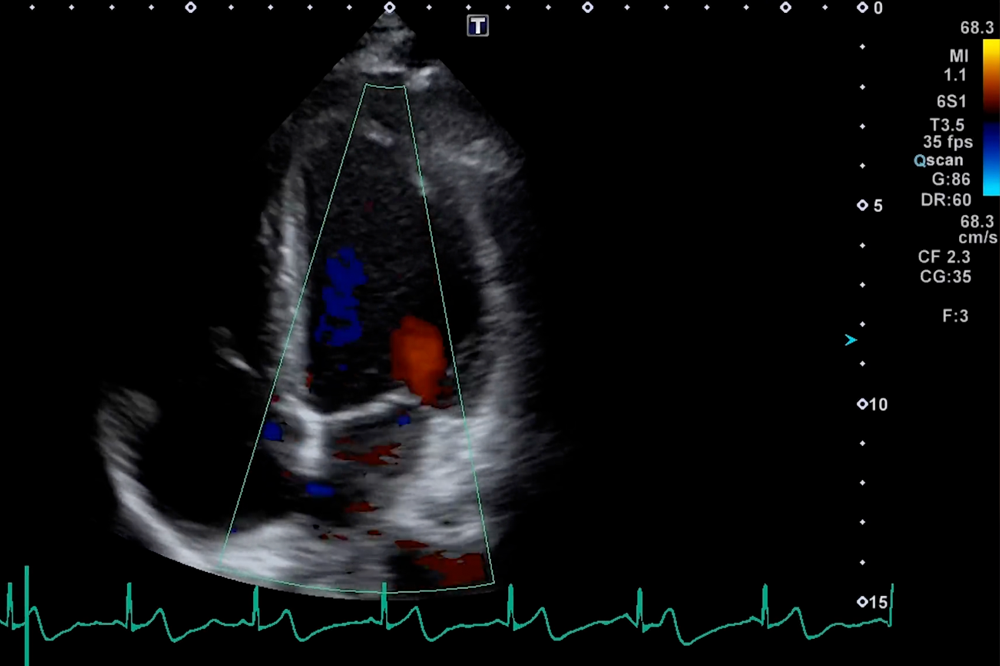

甲状腺・乳腺・心臓・腹部・骨盤など多部位の高精細検査に対応。乳腺検査ではAI画像解析も活用され、リアルタイムでの診断補助が可能です。